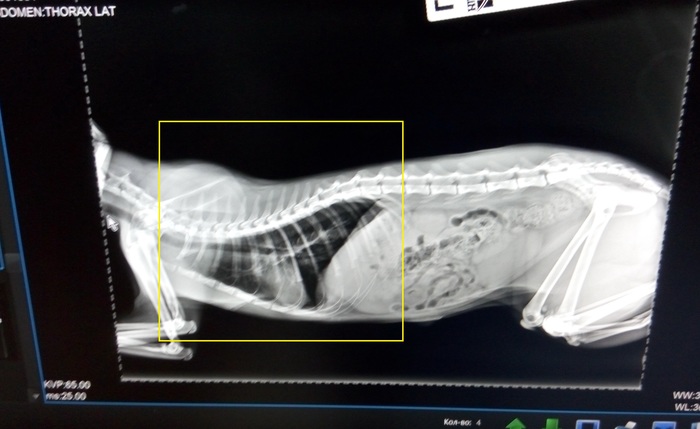

Рентген снимок Васьки сегодня

Вчера утром ко мне домой заезжал ветврач и осмотрел его. Сказал что вероятнее всего у него отек легких. Назначил ему уколы. Вчера вечером мне привезли все назначенные ему лекарства из интернет магазина, и я думал начать сегодня его лечение. Рентген мы решили ему пока не делать (у меня, у самого со здоровьем уже тоже давно не все хорошо) и мы подумали, что я начну давать лекарства и следить за его дальнейшим состоянием. Но сегодня к утру ему стало хуже и всё пошло по худшему из возможных варианту. Позвонил знакомому и привели его в ветклинику. Там ему сделали рентген, но он не получился и его стали делать второй раз. Потом ему сделали укол и хотели уже подключить к кислороду, но сердце его не выдержало и остановилось. Вернуть снова его к жизни, к огромному сожалению, у врачей уже не получилось. (((((

Врач сказал что возможно у него отек легких НОо в том, что это был отек легких, я не был уверен (мне кажется, что и ветврач который его осматривал тоже), так как разных возможных вариантов похожего состояния кошки или кота может быть очень много разных.

К чему я тут это всё написал и выложил это видео?! Если у вашего кота или кошки, вдруг когда-нибудь будет что-то похожее, то НЕЗАМЕДЛИТЕЛЬНО (!!!) везите их на рентген!